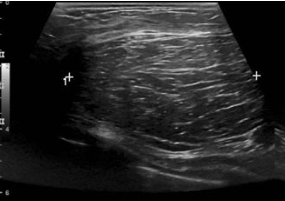

Fibroadenoma

Proliferation of fibrous (fibro) + glandular (adenoma) tissue

• Most common benign tumour

• Hormone-sensitive

• Enlarge during pregnancy/ lactation

• Decrease post menopause

Present:

• Young women (< 30)

• Mobile palpable lump

• Slow growing

• Sudden pain → hemorrhage

Treatment:

- Biopsy if enlarging

Oval or macrolobulated mass

Hypoechoic

Well circumscribed/ smooth margins

Homogeneous

Wider than tall

Posterior enhancement

Can have:

• *- Calcifications**

• *- Internal vascularity**